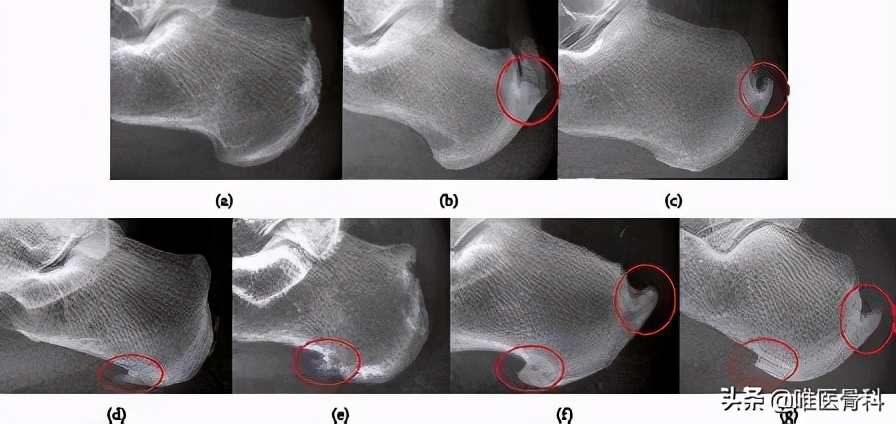

三、跟骨骨刺

许多中老年人,做足放射线可以看到跟骨结节附近有大小不等的骨刺。

当然,虽然很多人都有骨刺,但是只有一部分人的骨刺会导致足跟疼痛。

另外,也有一些研究显示,患者疼痛的程度跟骨刺的大小是没有关系的。很多有严重骨刺的患者并没有表现出足底疼痛症状。

但是骨刺方向跟疼痛还是有关的,研究表明,如果骨刺的方向是斜向前下方的时候,疼痛就非常明显了。